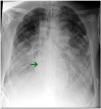

However, every technique has potential complications. In fact, up to 10% of all bicaval cannulas may experience migration or malapposition after insertion, with the distal end being able to progress into cardiac chambers, thus posing a risk of perforation, or even appearing to be in the normal position by fluoroscopy (in the inferior vena cava) while actually lodged in suprahepatic veins, as shown in the example (Fig. 2 and Video). This complication results in decreased drainage flow due to the inability to suction the lower territory, thus leading to inadequate oxygenation of the patient. Therefore, the use of fluoroscopy, along with ultrasound control to confirm the proper position of the ECMO cannula and subsequent monitoring at the ICU setting is increasingly advised.4